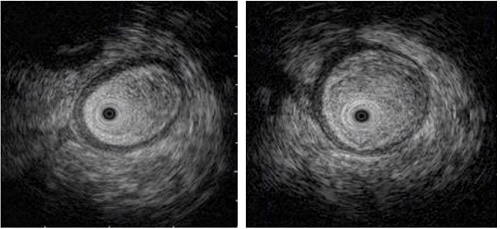

El estudio se complementó mediante una ecoendoscopia (Figura 4), en la cual se determinó la presencia de un edema de la pared del asa. Dados estos hallazgos, se sugirió una alta sospecha de enteritis por radiación, por lo que el paciente fue revalorado en cirugía gastrointestinal y se consideró que, ante la no mejoría, el individuo podría beneficiarse con un manejo quirúrgico. Por tanto, se realizó una remodelación de la anastomosis y en el reporte de histopatología no se halló una recaída tumoral.